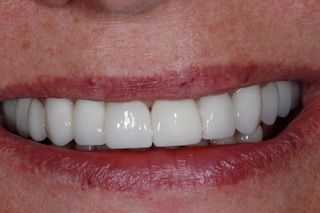

Bazując na wieloletnim doświadczeniu, oferujemy najkorzystniejsze dla każdego pacjenta rozwiązania protetyczne w technice 3D z wykorzystaniem skanera wewnątrzustnego wsparte uprzednią dokładną diagnostyką z użyciem tomografii komputerowej spiralnej. Współpracujemy z wyspecjalizowanym laboratorium, które tworzy prace w protokole DSD (digital smile design).

• Odbudowy na implantach Straumann i Neodent.

• Licówki porcelanowe

• Korony cerkonowe

Został mi wybity ząb górna jedynka. Na chwilę obecną mam protezę. Nie czuję się z nią dobrze. Jakie może być inne rozwiązanie?

Oczywiście, rozwiązaniem tego problemu może być wszczepienie implantu, który jest zastępstwem dla naturalnego korzenia. Po wygojeniu na wszczepiony implant prosto mówiąc mocuje się koronę, która niczym nie odbiega od wyglądu naturalnego zęba.